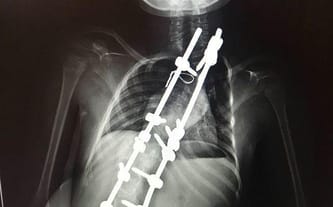

Było fajnie, wyprostowało się. Można było się cieszyć, że można iść, chodnikiem, czy łąką.. powoli ale jednak.. jak wszyscy.

Ale... się skrzywiło. Trochę... potem mocniej... a terez mocno.